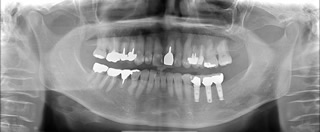

インプラント治療例1

• 1)平成24年10月9日 初診 62歳女性左下3本欠損

• 2)平成24年10月26日 インプラント3本埋入手術

3)平成25年2月19日 上部構造セット

• 4)治療後。現在もメンテ来院中。